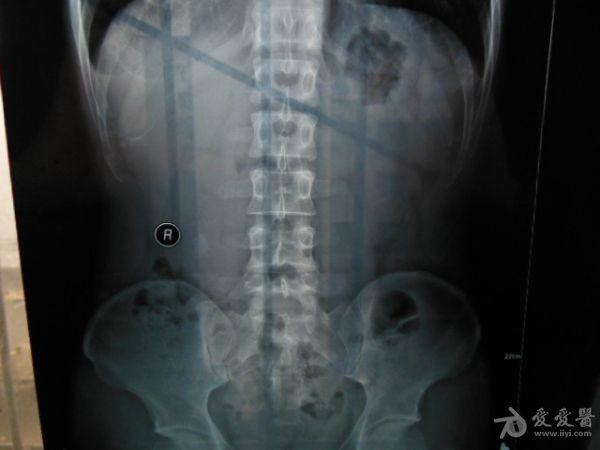

请老师看看这个腰椎和盆骨的平片有无问题

摔了一跤右臀着地,同时闪到腰,查出有椎间盘突出,目前是右臀麻木,整个右腿酸胀沉重。肌力正常走路正常,坐不到5分钟右腿就酸胀难忍。明显觉得左右**感觉不一样,右边软得多,

自觉下腰和盆骨感觉别捏,有歪斜感,扭腰时觉得舒服。腰4右侧一下有异物感。今天照了个腰椎正侧位和盆骨的正位平片,医生说没什么问题,拿来请各位老师看看腰椎和盆骨有没有错位,旋转,不等高等情况,再次感谢。

照该片看应该是骨盆旋移

这种症状拍平片没有什么意义,选择MRI或者CT吧

看片子没发现什么大的问题,没有骨折,没有增生。腰椎间盘突出做核磁共振最清楚。